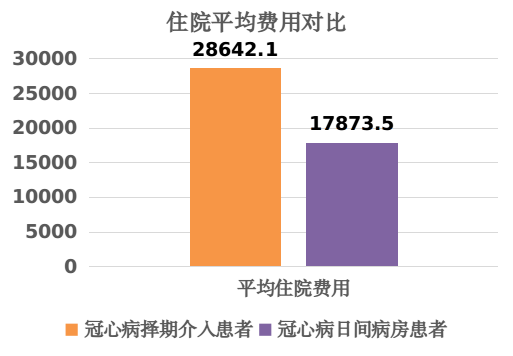

4.极大的降低了部分患者的经济负担、时间与精力的消耗,显著降低住院费用,减轻人民群众与政府的医疗负担。

在上级部门和领导的指导和支持下,冠心病介入“日间病房”模式得以迅速推广。通过严格的质量控制体系,确保手术的安全和有效,也确保住院当天术前准备和术后观察的高质量,极大的缩短了部分冠心病患者的就医时间和经济负担。同时,这种模式也需要患者具有良好的自我管理能力,积极配合医护人员的指导,共同为手术的成功和术后康复努力。

总之,冠心病介入“日间病房”模式是一种创新、务实、高效的医疗模式,为患者带来了福音。冠心病介入“日间病房”模式具备诸多优点,它在医疗领域拥有广泛的应用前景。随着医疗技术的不断进步以及人们健康意识的提高,这种高效率、低成本的医疗模式必将会受到越来越多医生和患者的青睐。在未来的发展中,我们相信这种模式将会得到更广泛的应用和推广,从而为更多的患者带来福音。

医务工作者不但需要去思考怎样去解决疾病本身的诊疗问题,还要努力在诊疗过程中提升效率与服务水平。我院心内科团队以此次患者的诊疗为契机,在广东省内率先针对合适的病人实行“冠脉介入手术当天出入院”的日间病房方案,在1天内完成临床诊疗工作和出入院,最大限度满足病人的健康需求和工作生活需求。这项基于自身技术自信基础上作出的优化和革新,从患者层面,患者以最舒适和便利的方式得到了高质量的冠心病综合治疗;从政府层面,老百姓以较低的费用接受了高质量的诊治,以更低的医疗支出提供了医疗保障。